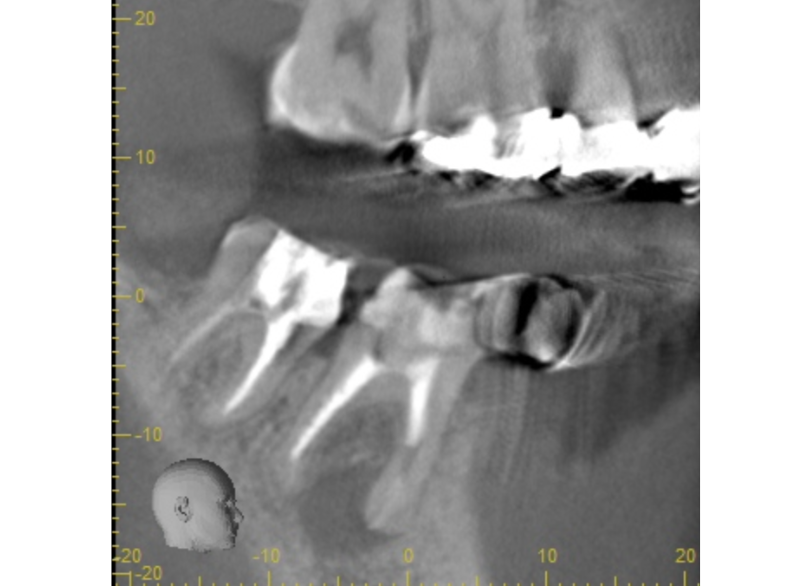

①失活による根管治療を行った

②術前CTによる根尖部の未治療および根尖透過像

| 診断 | 右下6.7根尖性歯周炎 | ||||

| 処置内容 (または主訴) | マイクロスコープ治療を用いた感染根管治療 | ||||